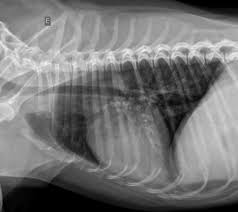

Canine bacterial pneumonia is a common respiratory disorder that may occur as a primary disease or secondary to aspiration, viral...

Bacterial pneumonia is defined as inflammation of the pulmonary parenchyma due to bacterial infection. In dogs, the most common forms include communit...

Introduction Bacterial pneumonia in dogs and cats presents with variable clinical severity, inconsistent laboratory findings and overlapping im...

Bacterial pneumonia remains the most commonly detected type of pneumonia in dogs and cats; however, fungal, parasitic an...